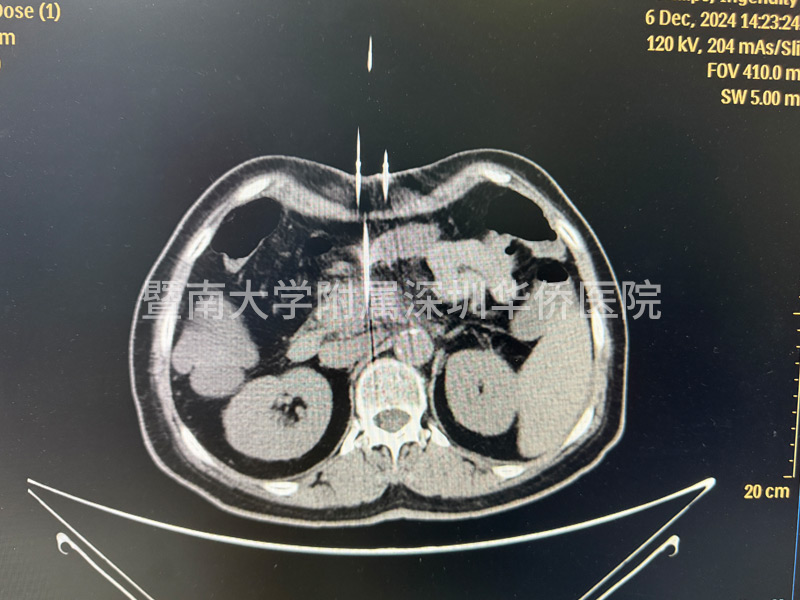

李女土的肿瘤在胰头位置,大小为2.8*3厘米,已经包绕肠系膜上动脉,失去了手术机会,在得知广东省应用了国产纳米刀治疗手术技术后,决定不远千里来到暨南大学附属深圳华侨医院,接受纳米刀消融手术。

上午11点,李女士正式进入手术室,多位相关领域专家,通过国产研发的新型设备正式对李女士进行手术,纳米刀消融技术适合中晚期的胰腺癌的治疗,这台手术设备在产品设计中,具有全球领先的核心技术,实现了在消融过程中,电压恰到好处,作用于细胞膜磷脂双分子层,形成不可逆电穿孔,诱导细胞凋亡,激活细胞免疫,经过几个小时的奋战,李女士成功完成手术治疗,此次纳米刀消融手术,顺利开展完成!

在超声或CT引导下,纳米刀治疗系统能够精确计算出消融区域的形状和体积,并告知探针的有效消融范围。治疗计划精确到毫米级别,为患者提供个性化的治疗方案。

纳米刀治疗后,显微镜下可见治疗区域和非治疗区域界限清晰。直径大于一毫米的血管、主要血管和导管均不受影响,继续维持正常功能。治疗后1-3个月,通过CT扫描几乎看不到治疗痕迹。